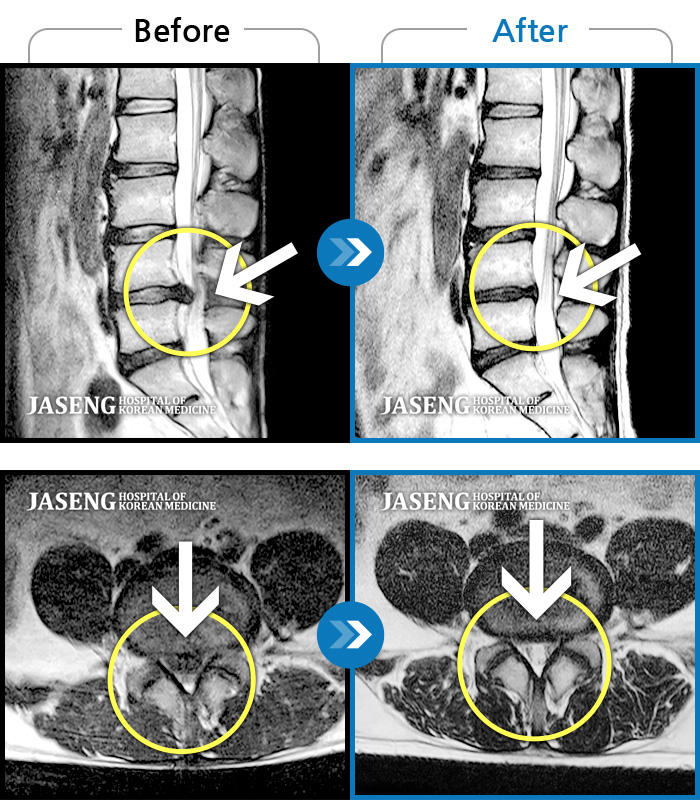

Before

After

환자에게 사전 동의를 받아 동일 조건에서 촬영되었습니다.

개인에 따라 치료 후 부작용이 발생할 수 있으니 의료진과 상담 후 치료를 진행하시기 바랍니다.

허리 통증이 극심하여 혼자 움직일수가 없었다.

앉지도 서지도 못하는 극심한 요통, 하지방사통으로 응급실 내원